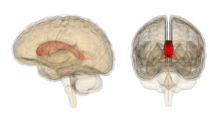

The corpus callosum (/ˈkɔːrpəs kəˈloʊsəm/; Latin for "tough body"), also known as the callosal commissure, is a wide, flat bundle of neural fibers about 10 cm long beneath the cortex in the eutherian brain at the longitudinal fissure. It connects the left and right cerebral hemispheres and facilitates interhemispheric communication. It is the largest white matter structure in the brain, consisting of 200–250 million contralateral axonal projections.

The posterior (back) portion of the corpus callosum is called the splenium; the anterior (front) is called the genu (or "knee"); between the two is the truncus, or "body", of the corpus callosum. The part between the body and the splenium is often markedly narrowed and thus referred to as the "isthmus". The rostrum is the part of the corpus callosum that projects posteriorly and inferiorly from the anteriormost genu, as can be seen on the sagittal image of the brain displayed on the right. The rostrum is so named for its resemblance to a bird's beak.

On either side of the corpus callosum, the fibers radiate in the white matter and pass to the various parts of the cerebral cortex; those curving forward from the genu into the frontal lobe constitute the forceps anterior, and those curving backward into the occipital lobe, the forceps posterior. Between these two parts is the main body of the fibers which constitute the tapetum and extend laterally on either side into the temporal lobe, and cover in the central part of the lateral ventricle.

Thinner axons in the genu connect the prefrontal cortex between the two halves of the brain; these fibres arise from a fork-like bundle of fibers from the tapetum, the forceps anterior. Thicker axons in the mid body, or trunk of the corpus callosum, interconnect areas of the motor cortex, with proportionately more of the corpus callosum dedicated to supplementary motor regions including Broca's area. The posterior body of the corpus, known as the splenium, communicates somatosensory information between the two halves of the parietal lobe and the visual cortex at the occipital lobe, these are the fibres of the forceps posterior.[1][2]